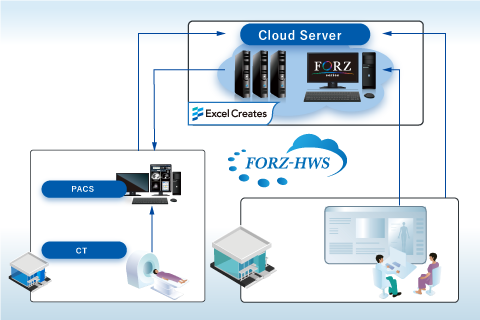

AI ソフト連携プラットフォーム・診断支援 クラウドデータ配信サービス FORZ-HWS

クラウドデータ配信サービス FORZ-HWS 装置共同利用サービス

健診システム FORZ-HWS(クラウドサービスシステム)

FORZ-HWS(クラウドサービスシステム)